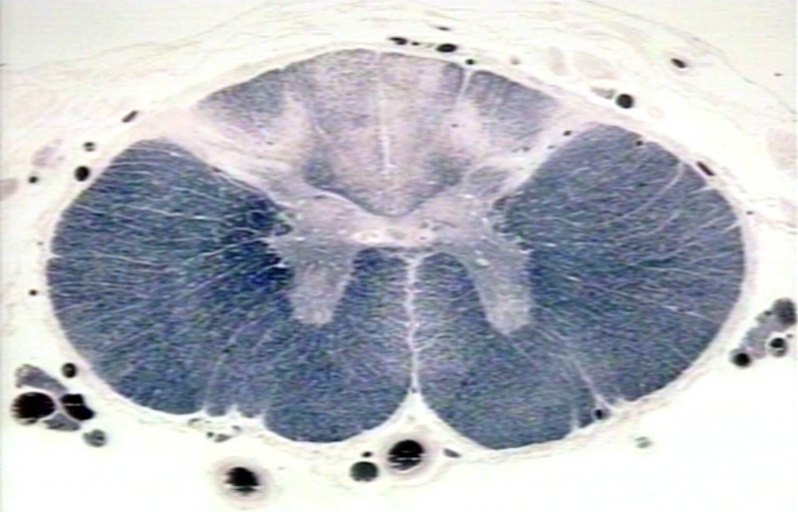

La neurosífilis es la invasión de las estructuras del sistema nervioso central por Treponema pallidum, y tabes dorsalis representa una de sus formas más avanzadas y debilitantes. La enfermedad afecta principalmente la médula espinal y la raíz dorsal, progresando lentamente y causando daño degenerativo parenquimatoso.

La invasión de las grandes fibras nerviosas mielinizadas por Treponema pallidum es respaldada por estudios, sugiriendo que esta acción bacteriana puede desencadenar la degeneración neuronal. La mielina, esencial para la conducción eficiente de los impulsos nerviosos, se ve comprometida, afectando así la función nerviosa normal.

En el análisis de la médula espinal afectada, se revela una infiltración celular significativa, donde células T-helper y macrófagos desempeñan roles prominentes. Las células T-helper, centrales en la respuesta inmune, se unen a los macrófagos, células fagocíticas capaces de destruir patógenos. La producción de citoquinas por estos macrófagos intensifica el proceso inflamatorio, contribuyendo al cuadro patogénico de la tabes dorsalis.